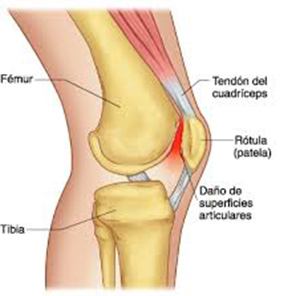

Cirugías de Rodillas

La artroscopia de rodilla es un cirugía en el cual la estructura interna de la articulación es examinada ya sea para realizar un diagnostico o para realizar un tratamiento, este procedimiento se realiza utilizando un instrumento parecido a un pequeño tubo llamado artroscopio.

La artroscopia de rodilla es un cirugía en el cual la estructura interna de la articulación es examinada ya sea para realizar un diagnostico o para realizar un tratamiento, este procedimiento se realiza utilizando un instrumento parecido a un pequeño tubo llamado artroscopio.